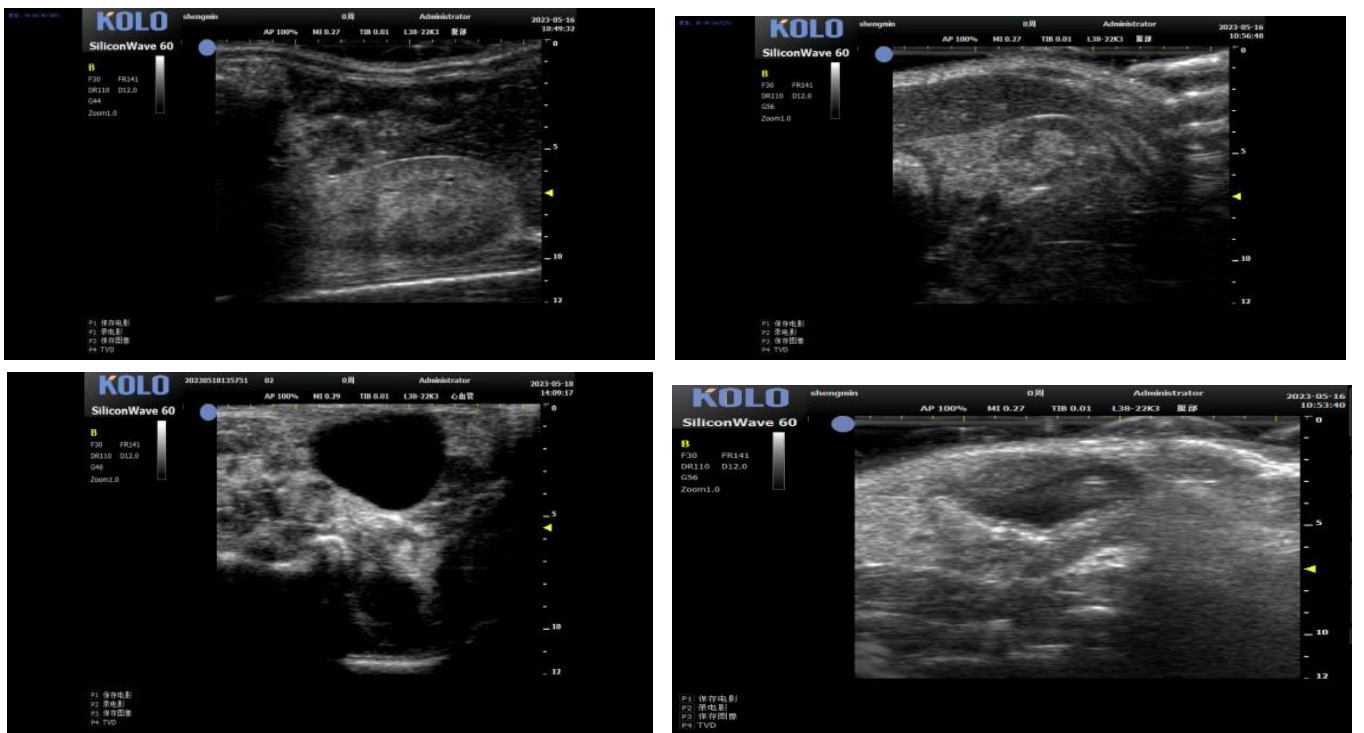

基于CMUT 半导体超声技术,集成多项发明专利,珂纳医疗精心研发出 SiliconWave 60 超高频小动物超声成像系统。该系统微米级的超高清分辨率,8-62 MHz 超宽频段和丰富灵敏的彩色多普勒功能为临床前科研用户观察小动物的心血管、腹部脏 器、浅表组织及胚胎等提供了清晰多彩的超声图像。系统的实时无创操作也为科研实验 的反复验证,长期动态观察等提供了极大的便利性。

3、小鼠血管方面研究

3.1 腹主动脉(长+短轴+管壁距离测量+血流流速)

3.2 颈动脉(长轴)